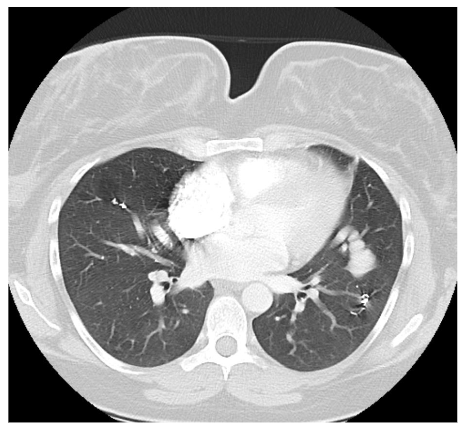

The recommended imaging studies were significant for numerous bilateral PAVM and she underwent placement of 10 total vascular coils antenatally. Unfortunately, the largest PAVM measured 32mm and was located within the left lingula, where a feeding vessel could not be identified. The next largest PAVM measured 17 mm (located in the right lower lobe) and 23 mm (located in the right upper lobe), both of which were successfully treated.

On postpartum day 1, the patient experienced an episode of acute onset hemoptysis, oxygen desaturation, tachycardia, and tachypnea. Prompt laboratory and imaging studies were obtained and pulmonology, anesthesia, and high-risk obstetrics were consulted. The patient immediately returned to the ICU where she was intubated due to persistent hypoxia. Repeat chest imaging was consistent with pulmonary hemorrhage. This was managed with urgent PAVM embolization, at which time a total of 4 vascular coils were placed in a right lower lobe PAVM that measured 17 mm. Notably, this was not one of the larger PAVMs targeted during antenatal embolization. The patient was subsequently extubated on postpartum day 3 and returned to the postpartum floor on postpartum day 4. The remainder of her hospital course was unremarkable and she was discharged home on postpartum day 5 in stable condition with appropriate follow up.